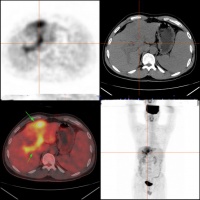

肝癌的影像诊断

影像学检查